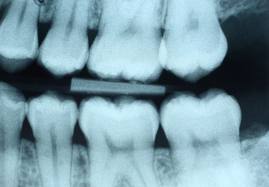

Adicionalmente, su dentista tomará radiografías de diagnóstico para revelar otros problemas ocultos. Se toma radiografías Bitewing cada 12 meses para detectar caries entre los dientes. Radiografías periapicales para una observación minuciosa de las raíces de los dientes así como de las estructuras adyacentes. Cada 3-5 años se toma una radiografía panorámica, la que involucra el uso de una máquina que gira alrededor de la cabeza, para examinar todo el maxilar, por si existieran problemas.